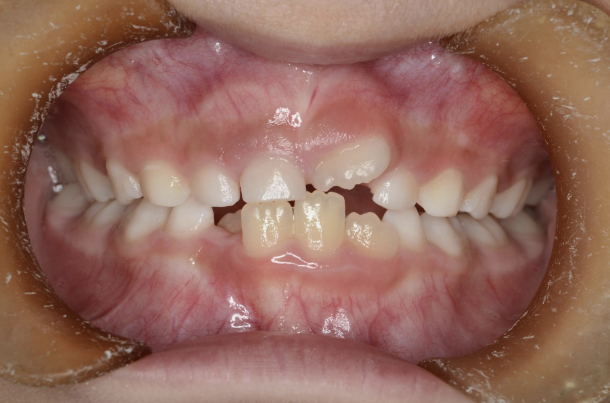

お子さんが「矯正治療」をはじめる時に直面する問題は 「装置が目立つ」、 そして「歯を抜く」ことがあげられます。

10歳を超えてからの治療開始ではそのようにならざるを得ないことが多いのです。

しかしながら、5〜7歳頃に治療をスタートすれば 目立ちにくい装置で、歯を抜かずに治療できることがあります。

10歳を過ぎてからの矯正治療の場合、大人の歯を抜いて治療することが多くなります。 一方、下の前歯が生えてくる5〜7歳頃から治療を始めると、大人の歯を抜かずに治療することが可能です。 抜かずに治療するには早期に治療を開始することが大切です。

歯並びが悪いのは、あごの骨が成長不足で小さいことで起こります。 当院で行なっているこどもの歯ならび治療はあごの骨に働きかけることができます。 骨に働きかけることで成長不足のお子さんの骨が成長して、顔つきが良い方向に変わっていく可能性があります。 実は大きくなってからの矯正治療は歯が並んでいるだけで骨やお顔つきは変わっていないのです。 5〜7歳ぐらいで治療を開始すると成長不足の骨に働きかけて、より良い顔つきになれる可能性があります。